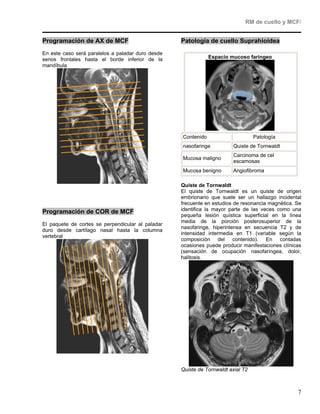

Contenido                      Patología

nasofaringe          Quiste de Tornwaldt

Carcinoma de cel

Mucosa maligno

escamosas

Mucosa benigno       Angiofibroma

Quiste de Tornwaldt

El quiste de Tornwaldt es un quiste de origen

embrionario que suele ser un hallazgo incidental

frecuente en estudios de resonancia magnética. Se

identifica la mayor parte de las veces como una

pequeña lesión quística superficial en la línea

media de la porción posterosuperior de la

nasofaringe, hiperintensa en secuencia T2 y de

intensidad intermedia en T1 (variable según la

composición del contenido). En contadas

ocasiones puede producir manifestaciones clínicas

(sensación de ocupación nasofaríngea, dolor,

halitosis.

Quiste de Tornwaldt axial T2